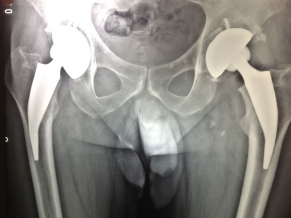

A través de la colocación de un sistema de prótesis que se arma dentro del cuerpo, el paciente vuelve a articular normalmente con su cadera. Esta técnica sirve para todas las edades, desde pacientes muy jóvenes hasta ancianos. Se usa para patologías diagnosticadas como la artrosis o necrosis de cadera, es decir, los infartos de cabeza de fémur.

“Son cirugías que tienen una duración aproximada de 40 minutos y los pacientes empiezan a caminar a las 24 horas de ser operados. Están internados uno o dos días y así se logran disminuir las complicaciones post operatorias, tales como la hemorragia, la pérdida de sangre o las trombosis en las piernas”, explicó Druetto. “Entre los 20 o 25 días están haciendo una vida normal y pueden efectuar actividad deportiva, dependiendo de la edad y características de cada paciente”.